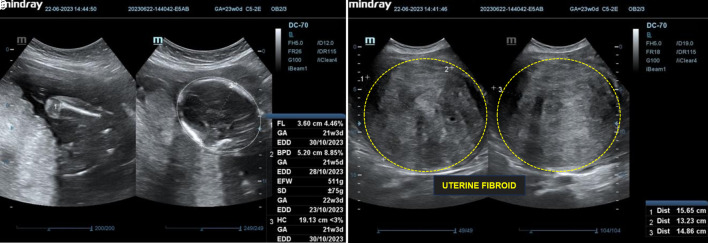

子宫肌瘤是一种良性肿瘤,影响了68.6%的女性,印度尼西亚的Hasan Sadikin医院报告的患病率在2.4%至12.46%之间。在怀孕期间,发病率降至0.1%至10.7%,但肌瘤仍可导致并发症。这个案例研究强调了一个复杂的妊娠与多个大子宫肌瘤的成功管理。孕36 ~ 37周的初迁症表现为子宫底1个大肌瘤(20 × 15 × 10 cm),前体6个小肌瘤。尽管面临这些挑战,但怀孕过程没有出现重大问题。进行了剖宫产手术,生下了一个体重2815克、身高46厘米的健康婴儿。该病例展示了对困难的产科情况的有效管理,强调了量身定制的护理和手术技巧在为母亲和婴儿实现有利结果方面的重要性。

Uterine fibroids, or myomas, are benign tumors affecting about 68.6% of women, with Indonesia's Hasan Sadikin Hospital reporting a prevalence between 2.4% and 12.46%. In pregnancy, the incidence drops to 0.1% to 10.7%, but fibroids can still lead to complications. This case study highlights the successful management of a complex pregnancy with multiple large uterine fibroids. A 36- to 37-week primigravida presented with a large intramural fibroid (20 × 15 × 10 cm) at the uterine fundus and six smaller fibroids in the anterior corpus. Despite these challenges, the pregnancy progressed without major issues. A cesarean section was performed, delivering a healthy baby weighing 2,815 g and measuring 46 cm. The case demonstrates effective management of a difficult obstetric situation, emphasizing the importance of tailored care and surgical skill in achieving favorable outcomes for both mother and baby.